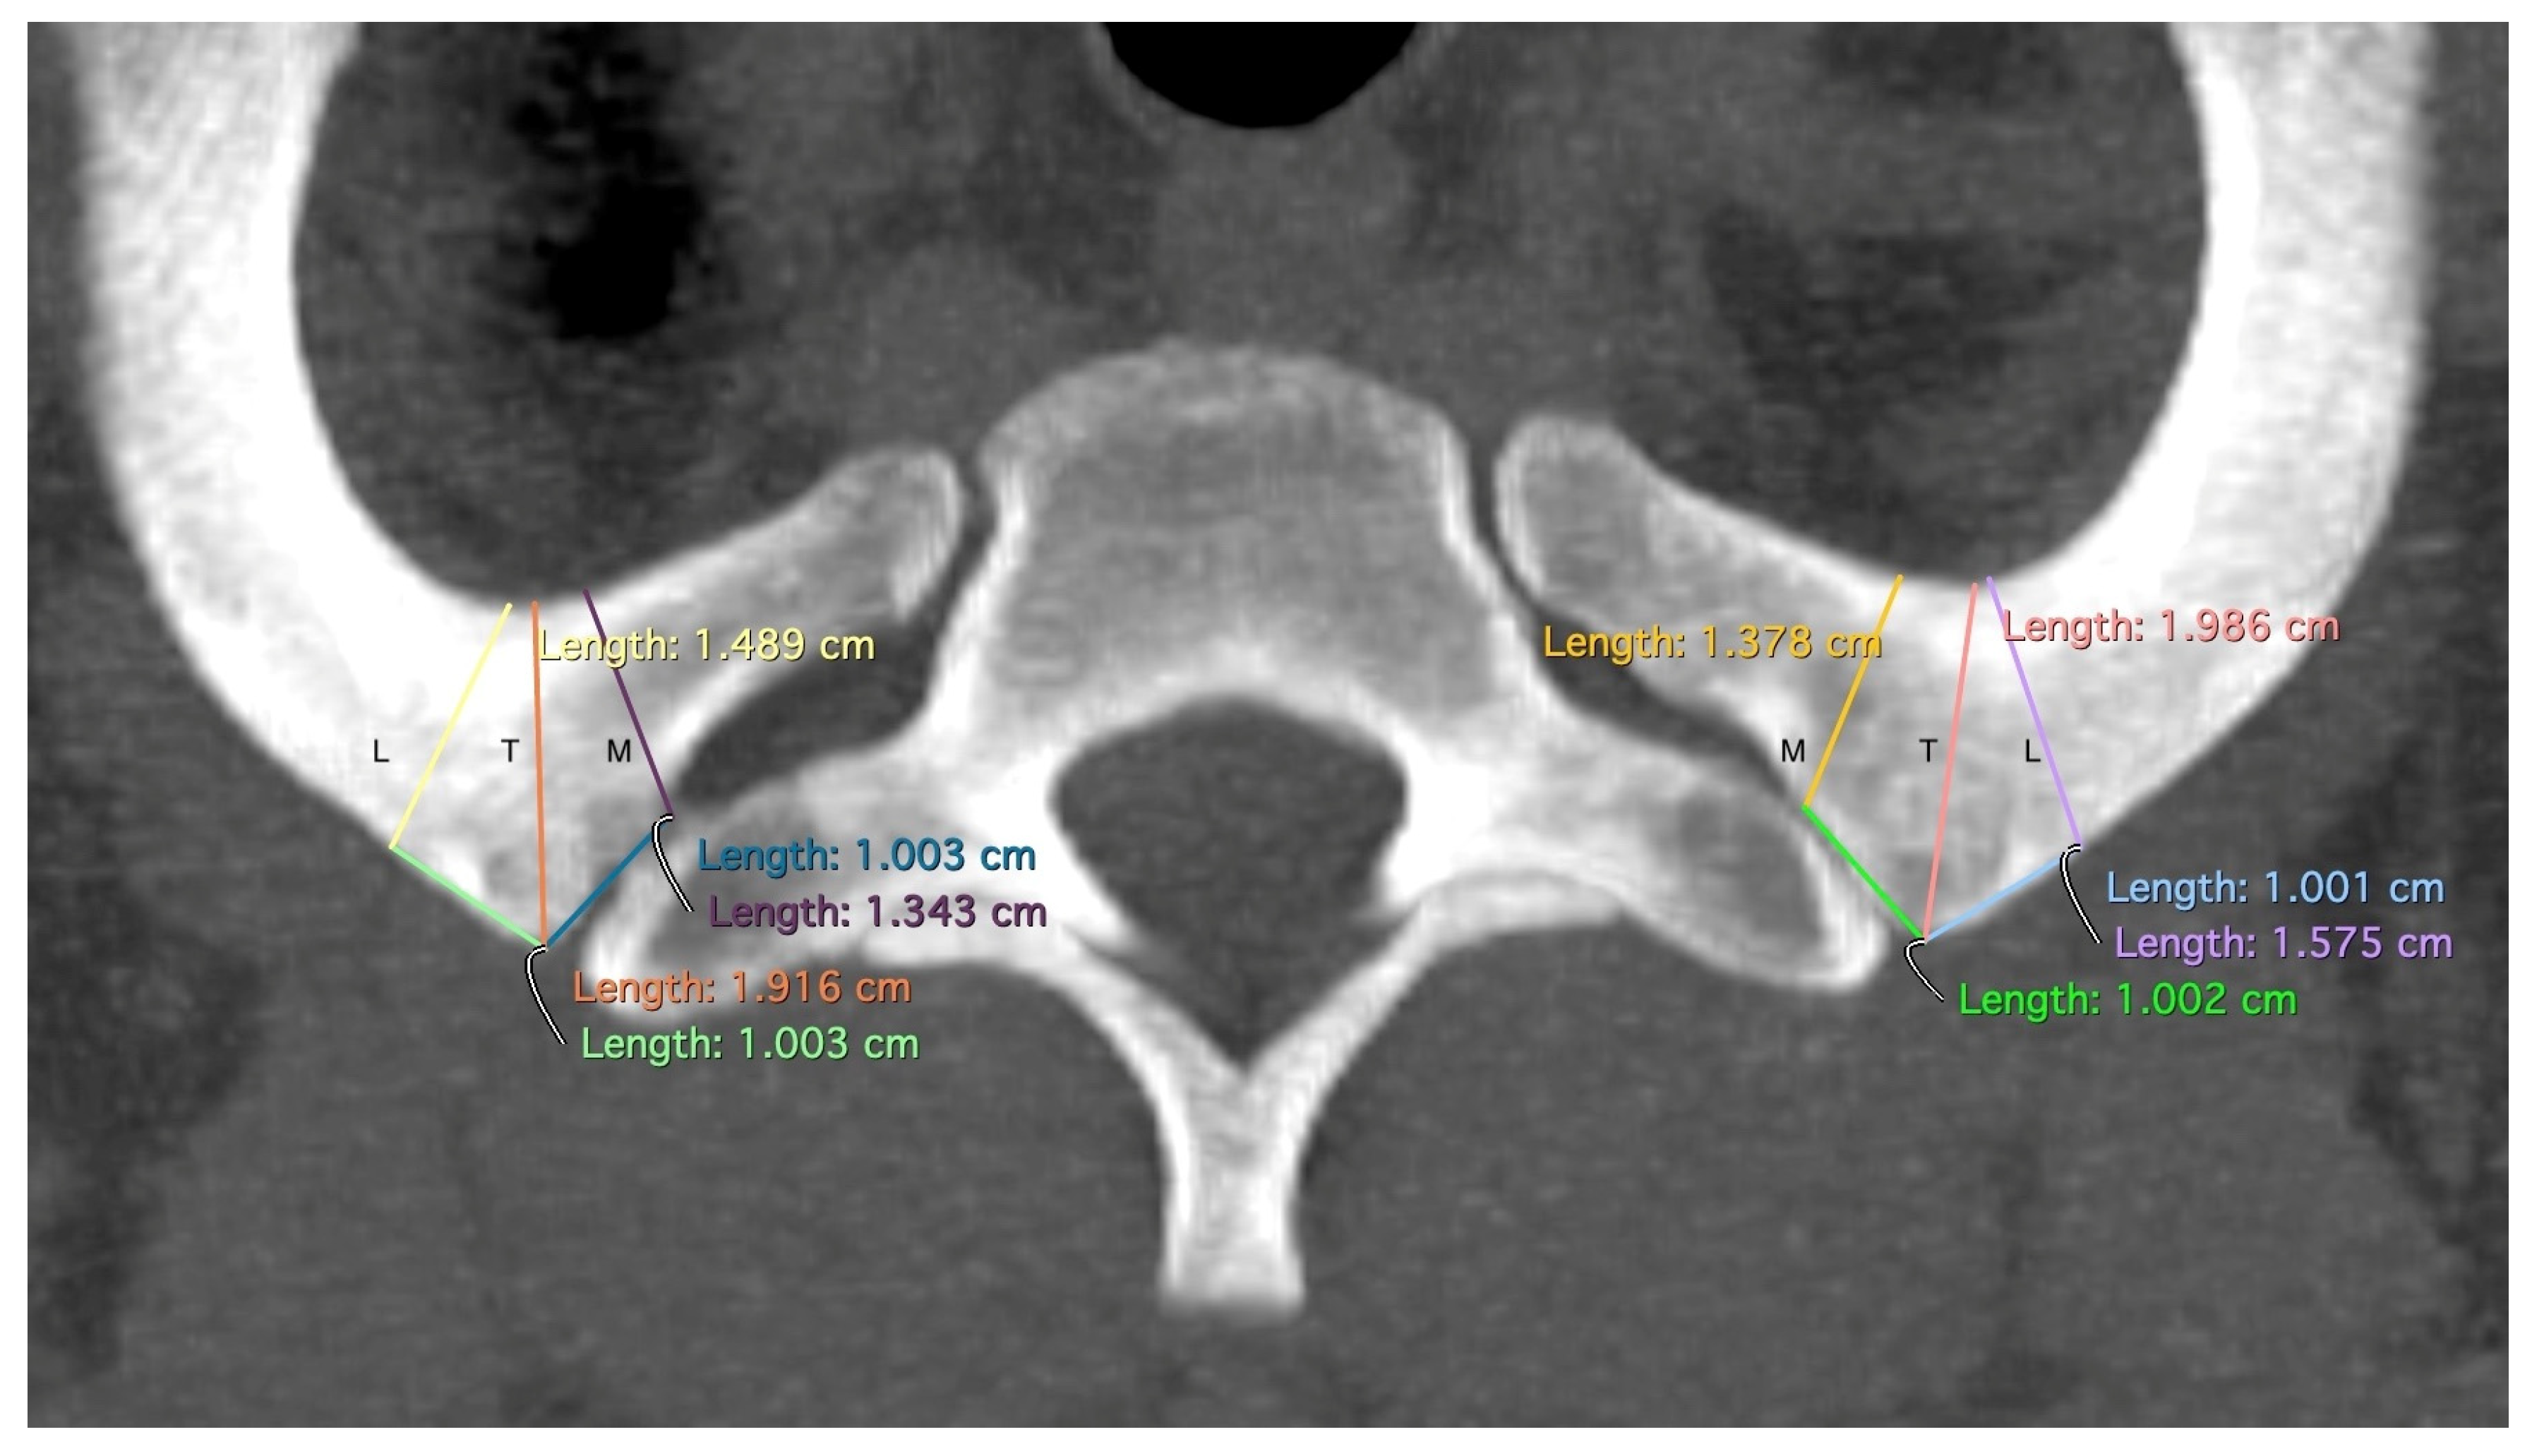

| Variable Name | Abbreviation | Description |

|---|---|---|

| Tuberculum | T | The minimal width of the rib at the level of the tuberculum costae 1 |

| Medial | M | The minimal width of the rib 1 cm medial to the tuberculum costae 1 |

| Lateral | L | The minimal width of the rib 1 cm lateral to the tuberculum costae 1 |